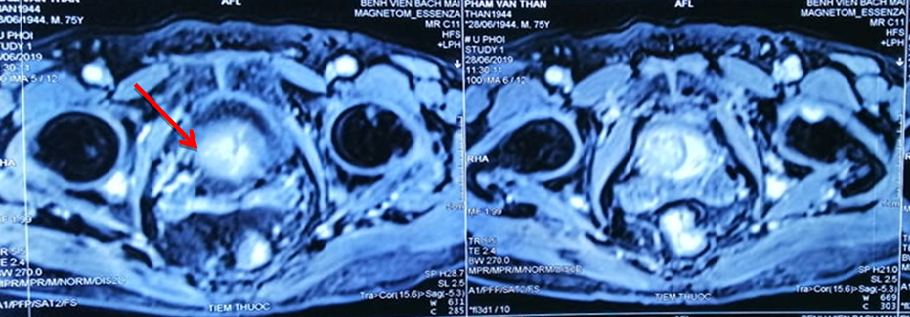

Khối u ở tuyến tiền liệt của bệnh nhân

Do 2 ung thư đều ở giai đoạn muộn, bệnh nhân có rất nhiều hạch ở trung thất, hạch thượng đòn, tổn thương xương đa ổ. Khối u ở phổi đã to 6x4 cm, 3 khối u não kích cỡ 0,5-0,7 cm, u tuyến tiền liệt to gần 3 cm.

Dù bệnh nhân tuổi cao nhưng sau 3 tháng, kết quả điều trị rất tốt, bệnh nhân đỡ khó thở, đỡ đau đầu. Sau 9 tháng, ông Thân hết khó thở, không ho, không đau tức ngực, tăng 3kg, hết tiểu khó, khối u ở phổi xơ hoá, khối u trên não biến mất, khối u tuyến tiền liệt giảm còn 2 cm.